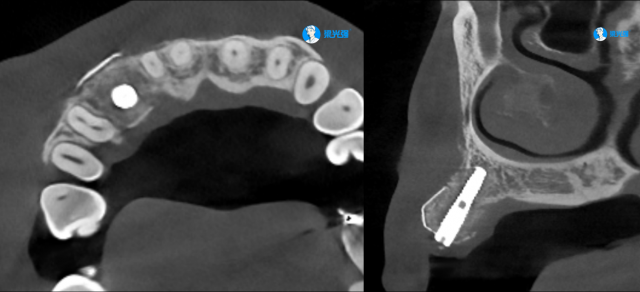

病例展示一

微信图片_2025-07-14_175225_999.jpg

微信图片_2025-07-14_175240_960.jpg